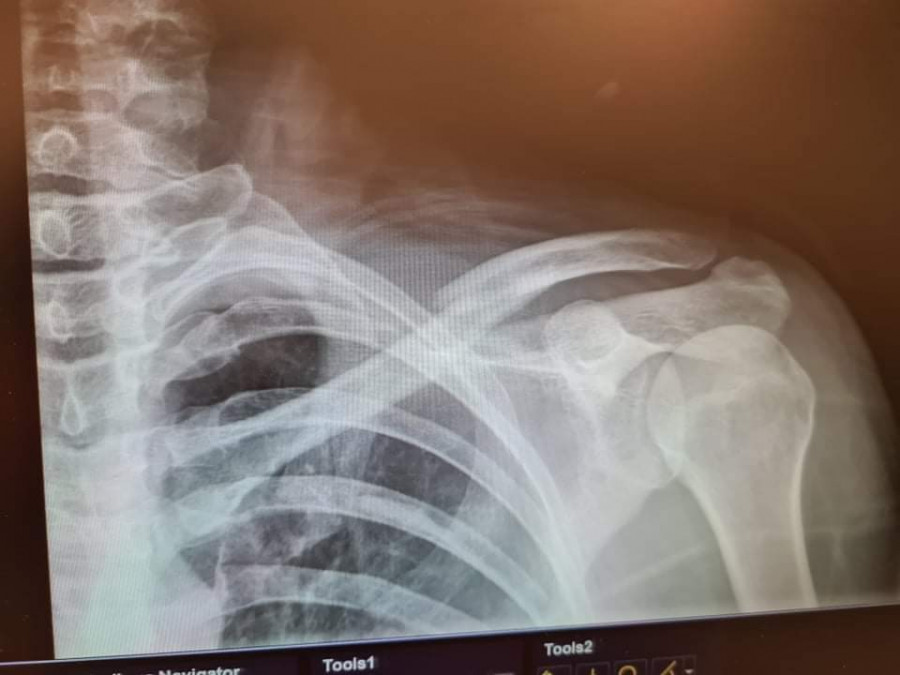

vicky2011 Oui c'est ça, ils n'opèrent que rarement car trop de risques de léser nerveusement voir d'hémorragies importantes (et effectivement 6 ans après je n'ai pas encore retrouvé la même qualité de sensation au niveau de la peau environnante et ai régulièrement des fourmillements très très agaçants vu que c'est un peu une démangeaison fantôme ), ils essaient autant que possible de réparer mécaniquement avec un cal osseux, mais dans mon cas ils ont quand même sérieusement merdé vu que dès le début il était assez flagrant que ça ne pouvait pas revenir en place mécaniquement

Stricto sensu de mémoire j'avais le "droit" de remonter dès les traits de fracture enfin comblés, mais tout en étant avertie qu'une nouvelle grosse chute pouvait faire de considérables dégâts vu que ça ne pêterais pas au niveau de l'osteosynthese mais a côté ... honnêtement j'ai tellement dégusté durant ces quelques mois et surtout avec la greffe osseuse qui s'en est suivie pour combler le bout d'os nécrosé ( du fait des mois d'attente )que je n'avais aucune envie de tenter le diable , je suis remontée au bout de quelques mois mais très occasionnellement, et refroidie , avec gilet airbag (puis projet bébé, puis elevage, donc ça a clairement marqué un tournant dans ma vie equestre , autant je n'avais pas d'appréhension de chuter avant autant désormais ce n'est plus le cas, pourtant sur le coup ça allait, c'est vraiment les mois de galère et douleur qui m'ont un peu "traumatisé"je pense ); je n'ai osé remonter sans airbag qu'une fois les broches retirées